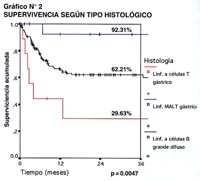

En el Gráfico N° 2, se agrupa a los pacientes con Linfomas a células B grande difuso, a los Maltomas Gástricos y a los pacientes con Linfoma a células T (anaplásicos, periféricos y del adulto), y cuando se les compara, se obtiene una clara diferencia en cuanto a supervivencia, con el mejor pronóstico para los Maltomas con más del 90% de sobrevida a 3 años, y como contrapartida, con el más bajo índice de supervivencia están los Linfomas a células T con el 30% , y el grupo de Linfomas a células B grande difuso, que es el grupo mayoritario, tiene una sobrevida mayor del 60%, expresando las curvas del gráfico una significancia estadística de p=0.0047.